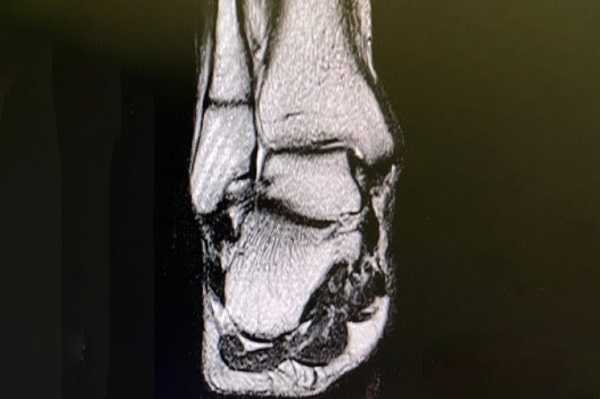

КОМПЬЮТЕРНАЯ ТОМОГРАФИЯ в диагностике повреждений стопы и голеностопного сустава

Какие методы лучевой диагностики используются при травмах стопы и голеностопного сустава? Какие преимущества имеет компьютерная томография по сравнению с рутинной рентгенографией? Возможно ли при помощи компьютерной томографии определить эффективность про

Возможно ли при помощи компьютерной томографии определить эффективность проводимого лечения?Переломы костей стопы и голеностопного сустава являются самыми частыми травматическими повреждениями скелета. Их доля, по свидетельству разных авторов, составляет не менее 10-15%.

Особенностью переломов костей области голеностопного сустава является высокая частота внутрисуставных повреждений. Разрушение суставных хрящей и субхондральных пластин существенно отягощает течение заболевания, ухудшает прогноз лечения и реабилитации таких больных. Неудовлетворительные результаты при лечении внутрисуставных переломов голеностопных суставов составляют до 28%.

Аналогичная тенденция прослеживается при переломах костей стопы. Наибольшее клиническое значение имеют повреждения пяточной и таранной костей. Так, переломы пяточной кости составляют около 60% от переломов костей предплюсны и 2% — от всех переломов. Результаты консервативного лечения чаще неудовлетворительные. Переломы пяточной кости в 75% случаев вовлекают подтаранный сустав, при этом 80% из них сопровождается смещением отломков. Отсюда несоответствие и нарушение конгруэнтности суставных поверхностей, ранние дегенеративные изменения, поздние болевые атаки и инвалидизация.

Однако рентгенография не может предоставить всю необходимую для травматолога информацию. Поэтому пациенту с переломом голеностопного сустава показано проведение рентгеновской компьютерной томографии (КТ).

Главным преимуществом компьютерной томографии является возможность детального изучения горизонтальной суставной поверхности большеберцовой кости. Нередко при КТ выявляются дополнительные линии перелома и отломки. КТ позволяет точно определить общую площадь суставной поверхности отломков, диастаз между ними, угловое и мультипланарное смещение, положение мелких осколков.

Главным преимуществом компьютерной томографии является возможность детального изучения горизонтальной суставной поверхности большеберцовой кости. Нередко при КТ выявляются дополнительные линии перелома и отломки. КТ позволяет точно определить общую площадь суставной поверхности отломков, диастаз между ними, угловое и мультипланарное смещение, положение мелких осколков Стресс-переломы костей предплюсны выявляются не более чем в 9% случаев. Они носят название «маршевых переломов», хотя встречаются не только у военных, но и у спортсменов и просто тучных людей.

Таким образом, травматическое повреждение стопы и голеностопного сустава требует расширенного рентгенологического исследования. Компьютерная томография должна стать рутинным методом исследования этой области ввиду высокой ее информативности. Появляющееся в последние годы новое программное обеспечение компьютерных томографов позволяет прогнозировать еще больший интерес к данному методу исследования со стороны травматологов. Так, компьютерная дизартикуляция предоставит полную пространственную информацию о состоянии суставных поверхностей. Режим флюороскопической компьютерной томографии позволит проводить малые инвазивные мероприятия под контролем КТ в реальном режиме времени. Все это обещает рост числа научных исследований по рентгеновской компьютерной томографии больных травматологического профиля в ближайшие годы.